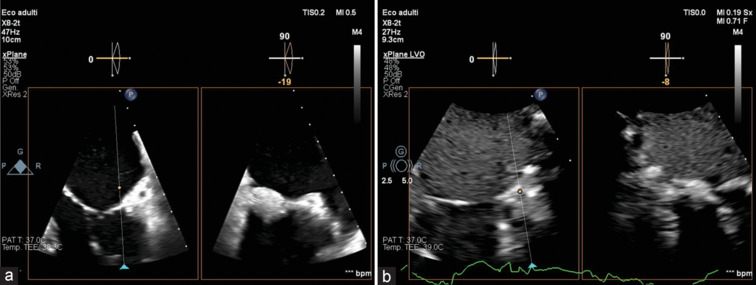

Caseous calcification of the mitral annulus (CCMA) is a rare variant of mitral annular calcification, and a multimodality approach is advised to ensure an accurate diagnosis. We report a case of a patient with CCMA, associated with severe mitral regurgitation. An 82-year-old woman was admitted due to worsening heart failure. Transthoracic echocardiography revealed a fixed, hyperechogenic mass, accompanied by restriction of the posterior mitral leaflet, and subsequent severe mitral regurgitation. Transesophageal echocardiography demonstrated a restricted motion of the posterior mitral leaflet, because of a large, echogenic mass (15 mm × 11 mm), attached to the mitral annulus, vacuolated with a central echolucent aspect, lacking acoustic shadowing. Contrast-enhanced cardiac computed tomography identified a distinct oval mass (18 mm × 11 mm × 19 mm) presenting a central hypodense content and peripheral calcification, strongly suggestive of CCMA. Considering the patient's profile, surgical valvular replacement was considered unsuitable. Therefore, a transcatheter edge-to-edge repair was performed, resulting in mild residual regurgitation.